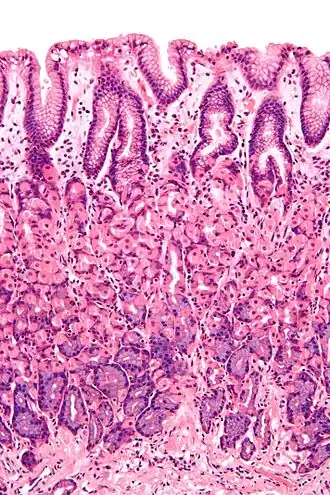

Mucosa ou membrana mucosa é um tipo de tecido epitelial de revestimento interno das cavidades do corpo que têm contato com o meio externo.[1]

"O epitélio do intestino delgado, por exemplo, é constituído por uma camada simples de células cilíndricas, que lhe permitem executar sua principal função: absorver o alimento. Por isso, essas células possuem dobras - as microvilosidades ou microvilos -, que aumentam a área de absorção do alimento. Nesse caso, a proteção do organismo é feita pelo muco, substância viscosa formada por glicoproteínas e produzida por células especiais - as células caliciformes -, encontradas em vários órgãos."

Mucosa é o nome dado ao conjunto formado por epitélio mais tecido conjuntivo que reveste as cavidades úmidas do corpo, em contraste com a pele onde a superfície é seca. Portanto, recobre locais como a boca, intestino, bexiga, etc. Seu tecido conjuntivo é denominado lâmina própria ou córion.